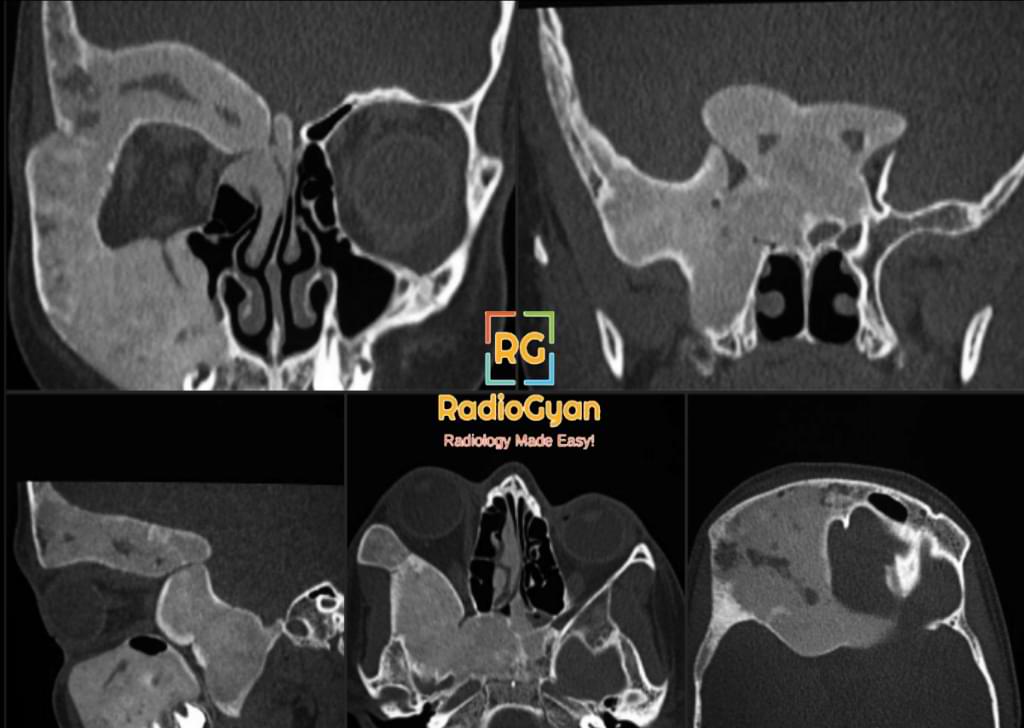

CT Features:

Typical ground-glass appearance as seen on radiographs.